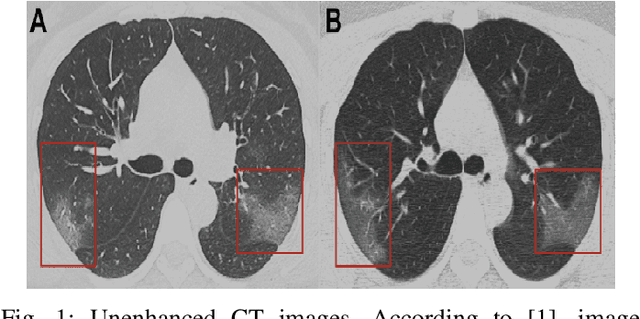

Abstract:One of the most serious global health threat is COVID-19 pandemic. The emphasis on improving diagnosis and increasing the diagnostic capability helps stopping its spread significantly. Therefore, to assist the radiologist or other medical professional to detect and identify the COVID-19 cases in the shortest possible time, we propose a computer-aided detection (CADe) system that uses the computed tomography (CT) scan images. This proposed boosted deep learning network (CLNet) is based on the implementation of Deep Learning (DL) networks as a complementary to the Compressive Learning (CL). We utilize our inception feature extraction technique in the measurement domain using CL to represent the data features into a new space with less dimensionality before accessing the Convolutional Neural Network. All original features have been contributed equally in the new space using a sensing matrix. Experiments performed on different compressed methods show promising results for COVID-19 detection. In addition, our novel weighted method based on different sensing matrices that used to capture boosted features demonstrates an improvement in the performance of the proposed method.